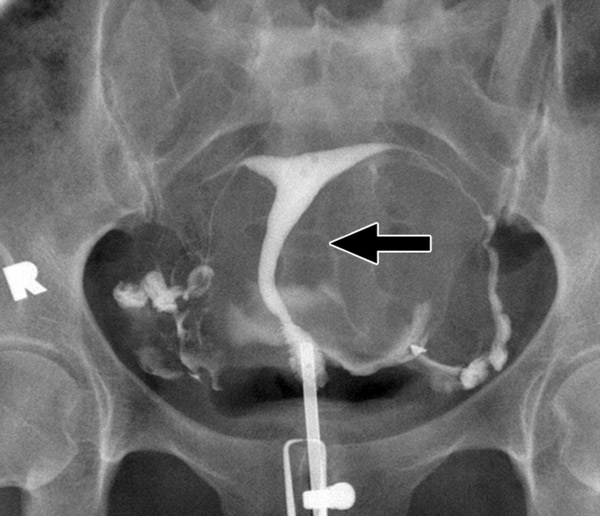

Гистеросальпингография: описание и фотографии